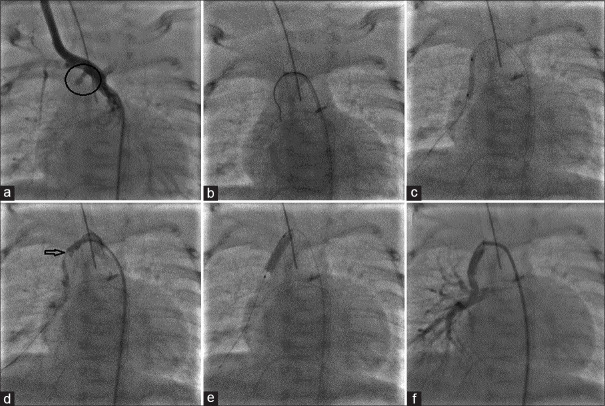

The modified Blalock-Taussig-Thomas shunt (mBTT shunt) is an effective palliation for cyanotic congenital heart diseases. However, a late obstruction of the mBTT shunt may present as a life-threatening complication. In this setting, a redo-surgery or a transcatheter recanalization is necessary to restore adequate pulmonary blood flow. We report three cases of transcatheter recanalization and stenting of a completely obstructed mBTT shunt, highlighting the tips and tricks of the percutaneous approach.

Abstract Image